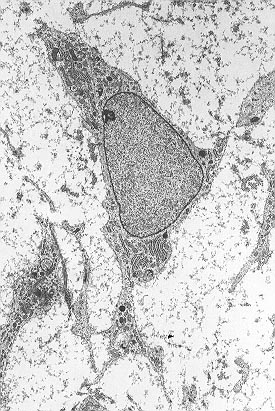

خلية جذعية متعلقة باللحمة المتوسطة

![]() خلية جذعية باللحمة المتوسطة تبين typical ultrastructural morphology. | |

الخلايا الجذعية المتعلقة باللُحمة المتوسطة إنگليزية: Mesenchymal Stem Cells هي خلايا جذعية بالغة لها القابلية على التمايز إلى عدة أنواع من الخلايا وأهمها: الخلايا بانية العظام والخلايا العضلية والخلايا الغضروفية والخلايا الشحمية والخلايا العصبية. يمكن الحصول على هذه الخلية من نخاع العظم.